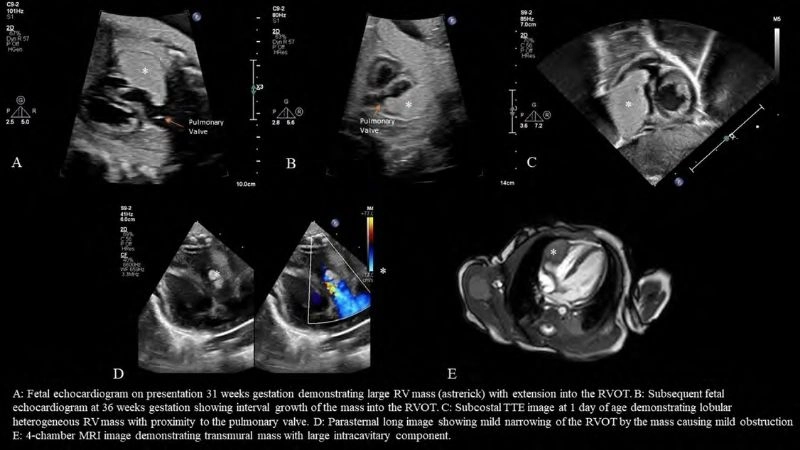

Images visual examples of rhabdomyoma

Rhabdomyoma is a rare benign tumor of striated muscle, commonly affecting the heart in children. Images often highlight cardiac masses that disrupt heart rhythm and function.

Detailed look at cardiac rhabdomyoma condition

Insightful capture of fetal rhabdomyoma findings